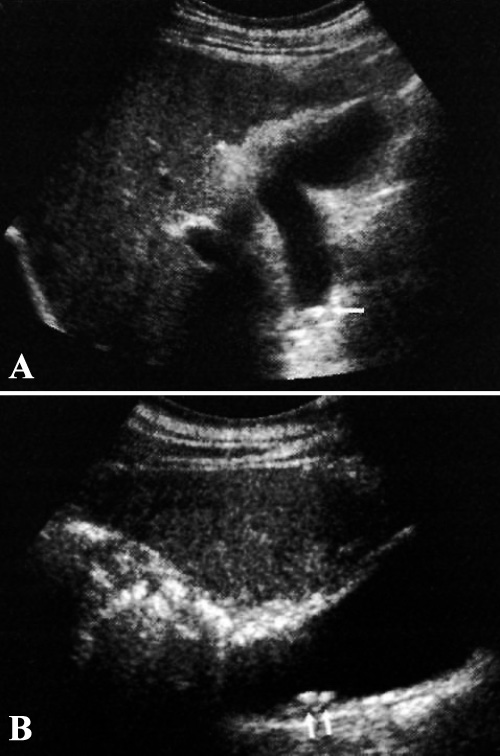

Следует применять максимальную частоту, чтобы обеспечить достаточное проникновение ультразвука в правом (датчик с частотой ≥ 3,5 МГц). При исследовании желчного пузыря следует использовать гармонические методики (фото 5).

Фото 5. Холелитиаз при использовании гармоник. А – продольный вид желчного пузыря без гармоник. В – продольный вид с гармониками. Оба изображения получены у одного и того же пациента в одном и том же положении тела. Стрелками обозначены желчные камни, которые без гармоник не визуализируются